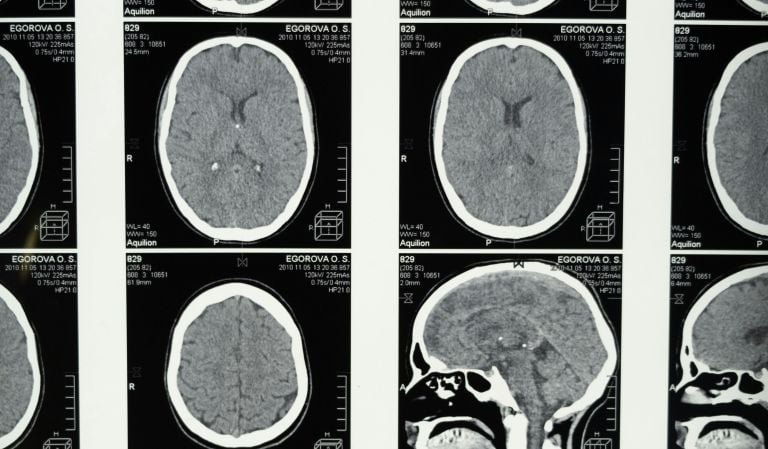

Human brains contain approximately 7 grams of plastic (equivalent to several bottle caps).

Brain samples from 2024 showed 50% MORE microplastics than samples from 2016.

Across numerous animal studies, microplastics consistently impair memory, learning, and social behavior - with concerning parallels to dementia. According to new research, microplastic concentrations were 3 to 5 times higher in the brains of patients with dementia, compared to cognitively normal brains. It’s not clear whether microplastics may cause or contribute to dementia, nor whether dementia-induced changes to the brain might allow more microplastics to enter.